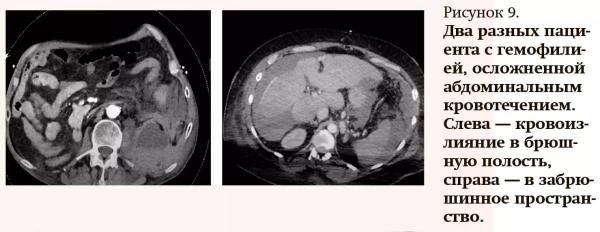

При лучевой диагностике тромбозов и кровотечений в брюшной полости чаще применяются УЗИ и КТ, как по отдельности, так и дополняя друг друга, реже — МРТ.

Причинами абдоминальных кровотечений могут быть различные травмы (не только в области живота, но и грудной клетки), острая и хроническая патология внутренних органов, состояния, связанные со снижением свертываемости крови (например, гемофилия), также это могут быть осложнения после хирургических вмешательств в постоперационном периоде. Чаще встречаются кровоизлияния в брюшную полость, гораздо реже — в забрюшинное пространство (см. рис. 9).